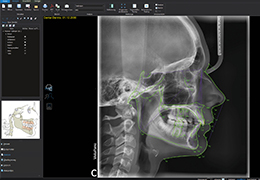

View X-Ray CT & MRI Scans Fast and Easily

Designed for surgeons, Pro Surgical 3D makes it easy to view patient scans quickly. Pro Surgical 3D facilitates the optimal 3D treatment and assessment workflows based on X-ray CT and MRI scans – and best of all, it’s FREE!

Traditional multi-planar slicing

Multi-planar slicing.

Oblique slicing.